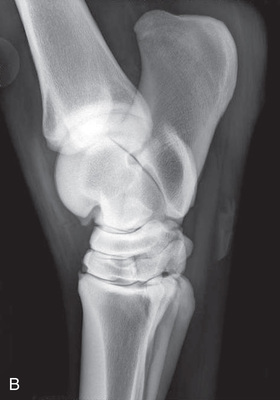

| Stifle | Lateromedial (LM) | Lateral (L) |

| Caudoproximal-craniodistal (CdPr-CrDi) | Caudocranial (CdCr) | |

| Lateral trochlear ridge and medial femoral condyle (stifle) | Caudoproximal 60-degree lateral–craniodistomedial oblique (Cd60L-CrMO) | CdLCrMO |

| Optional stifle | Cranioproximal-caudodistal (CrPr-CdDi) | Craniocaudal (CrCd) |

| Cranioproximal-craniodistal oblique(CrPr-CrDiO) | Skyline patella | |

| Lateromedial flexed (LM) | Flexed lateral (L) |

Radiography of the femorotibial joint (stifle) is difficult because of the thickness of the surrounding tissue and the sensitive nature of this region. Because of the depth of the muscle in the femoral region, the caudocranial projection demonstrates little above the joint space. Radiographs of this region should be attempted only if the patient is cooperative. Safety is paramount in radiography of the hind region of the horse. Sedation or a twitch may be used; general anesthesia is also to be considered.